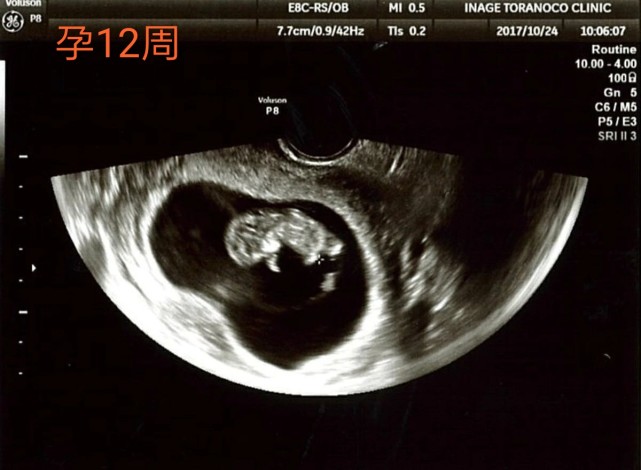

· 12週目の検診に行きました。 エコーで、赤ちゃん手足をぶんぶん動かして、ぐるんぐるんと前転しまくっていている姿が見れて、ほっとしました。 担当医からは、「もう安定期と言っていいでしょう、おめでとう。 · 12週で「安定期ですね」と言われました。 12週目の検診に行きました。 エコーで、赤ちゃん手足をぶんぶん動かして、ぐるんぐるんと前転しまくっていている姿が見れて、ほっとしました。 担当医からは、「もう安定期と言っていいでしょう、おめでとう。 」という言葉をいただきました。 とっても嬉しかったのですが、ふと疑問に。 安定期というのは5ヶ月目 · 妊娠12週で受検できる出生前診断 妊娠12週は、 妊娠初期から妊娠中期へと近づいていく時期 です。超音波検査のエコー写真では、胎児の見た目により人間らしさが出てきます。エコー検査のほかにも、出生前診断には多くの検査方法があります。

助産師監修 妊娠12週目 妊娠4ヶ月 のお腹の中の赤ちゃんの様子について

妊娠12週 妊婦の様子は 胎児の様子は おむつのムーニー 公式 ユニ チャーム

妊娠12週 たまひよ 医師監修 妊婦の症状や体の変化 赤ちゃんの成長